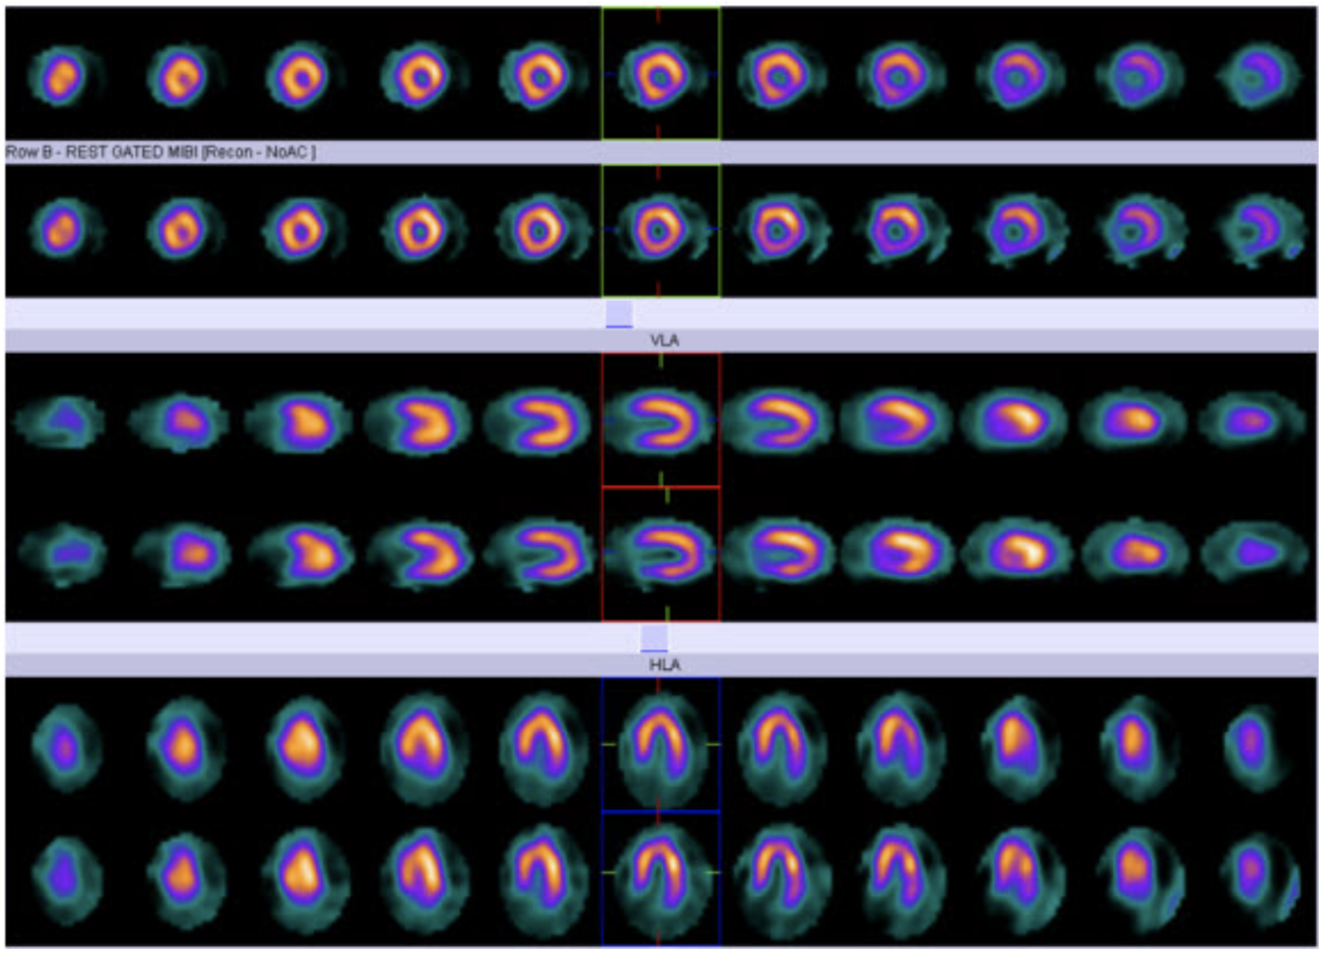

Based on the stress and rest projection images, which radioisotope imaging protocols was most likely use

1-day rest / stress Tc99m